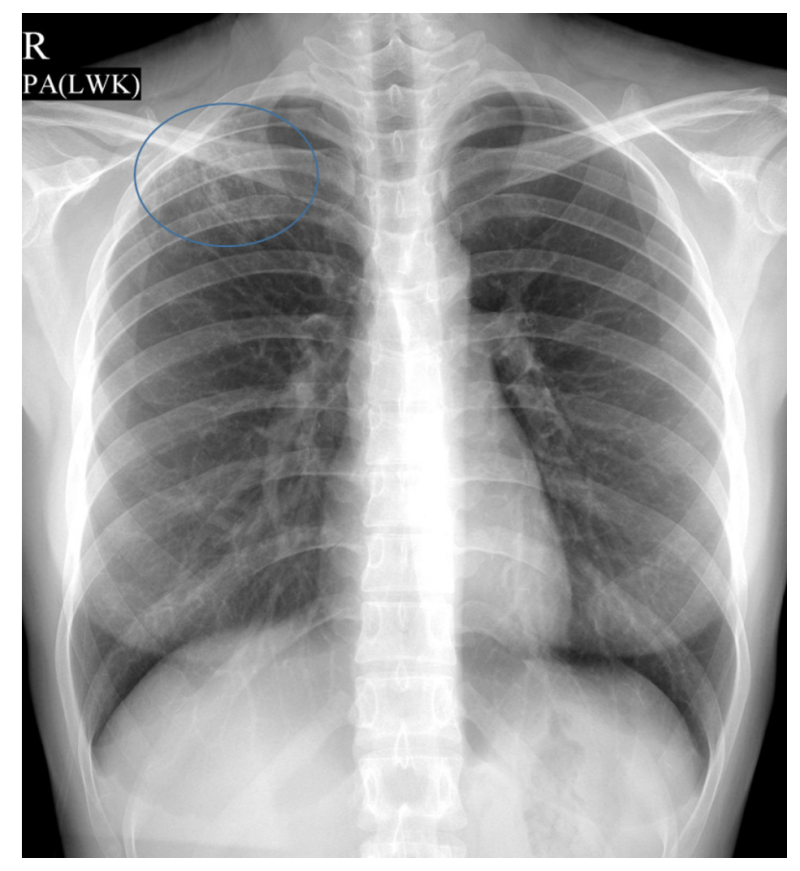

결핵은 주로 폐에 영향을 미치는 병이며, X-ray나 CT를 통해 결핵에 의한 변화를 확인할 수 있습니다. 초기에는 작은 점 같은 병변들이 있을 수 있으며, 진행된 경우에는 폐의 일부가 충혈되거나 손상될 수 있습니다. 이런 이미지는 결핵의 진단과 치료에 매우 중요한 역할을 합니다.